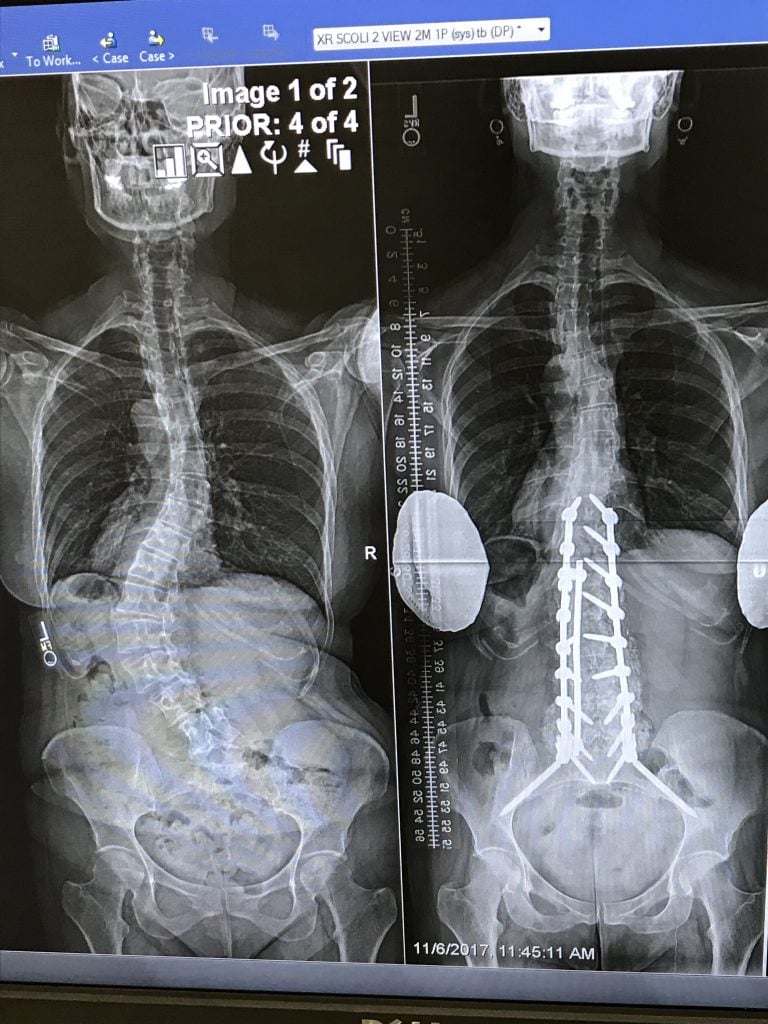

As June is National Scoliosis Awareness Month, I thought it would be a good time to post my “Back in the Game” story. I was diagnosed with scoliosis at age 15 and I subsequently wore a brace for two years, which held my moderate “S” curvature at bay until I stopped growing. Fast forward to age 50, my 3 times a week yoga practice had to stop due to pain, as well as bike riding, hiking, long walks and even standing in the kitchen to cook—my quality of life was deteriorating.

X-rays showed my curvature had dramatically worsened and my bone density was low for my age. I saw a local orthopedic surgeon, who said there was nothing he could do and he sent me to Pain Management, where I underwent numerous steroid injections and nerve ablations, which helped temporarily at first, but the pain kept coming back.